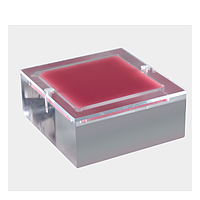

Another major group is imaging phantoms. Products from True Phantom Solutions illustrate how phantom-based testing supports modality validation, research, training, and protocol development. Depending on the application, users may need a Doppler phantom, an anatomical rat model, a newborn head, torso, arm, or a larger animal phantom for cross-modality studies.

Phantoms are especially useful when teams need a controlled target instead of relying on patient-dependent variables. The True Phantom Solutions DP-C01 Doppler Phantom For X-Ray CT, US, MRI is an example of a model intended for multi-modality work, helping users evaluate image behavior and flow-related or tissue-equivalent responses under repeatable conditions.

For anatomical and preclinical-style workflows, examples in this category include the True Phantom Solutions RT-C01 Rat Phantom (Cylindrical) For X-Ray CT, MRI and the True Phantom Solutions RT-A02 Rat Phantom (Anatomical) For X-Ray CT, US. There are also neonatal-focused models such as the HD-N01, HD-N02, and HD-N03 newborn head variants, the AM-S01 newborn arm, and the AN-N01, AN-N02, and US-N02 newborn torso models. These products are relevant when users need tissue-mimicking structures for imaging evaluation, educational use, or method development.

Users should also consider sample form factor and use case. A compact tissue-equivalent insert or small anatomical model may be suitable for focused validation, while a larger and more detailed phantom may be more useful for protocol testing, research, or training. Where output values and safety-related behavior must be checked, teams may also compare their broader toolkit with instruments such as a multimeter for general electrical troubleshooting, although biomedical verification itself requires application-specific equipment.